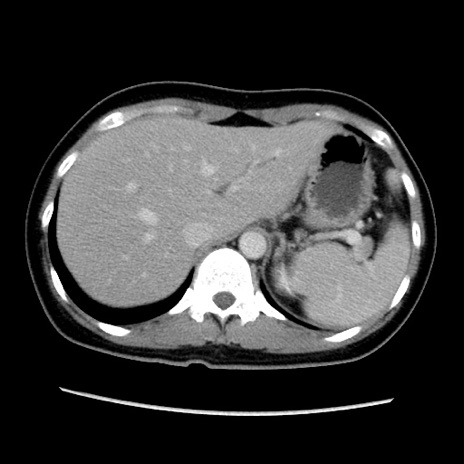

症例39(横断像)

【症例】40歳代女性

【主訴】上下腹部痛

【現病歴】2日目から下腹部痛あり。夜間は痛みで眠れなかった。昨日より上腹部痛と下痢が出現。臥位で痛みは軽快したため、休んでいた。本日になって臥位でも立位でも痛みが強くなってきたため救急要請。

【既往歴】子宮内膜症

【身体所見】部:平坦・軟、左上下腹部に圧痛あり、反跳痛あり。

【データ】WBC 21800、CRP 26.78